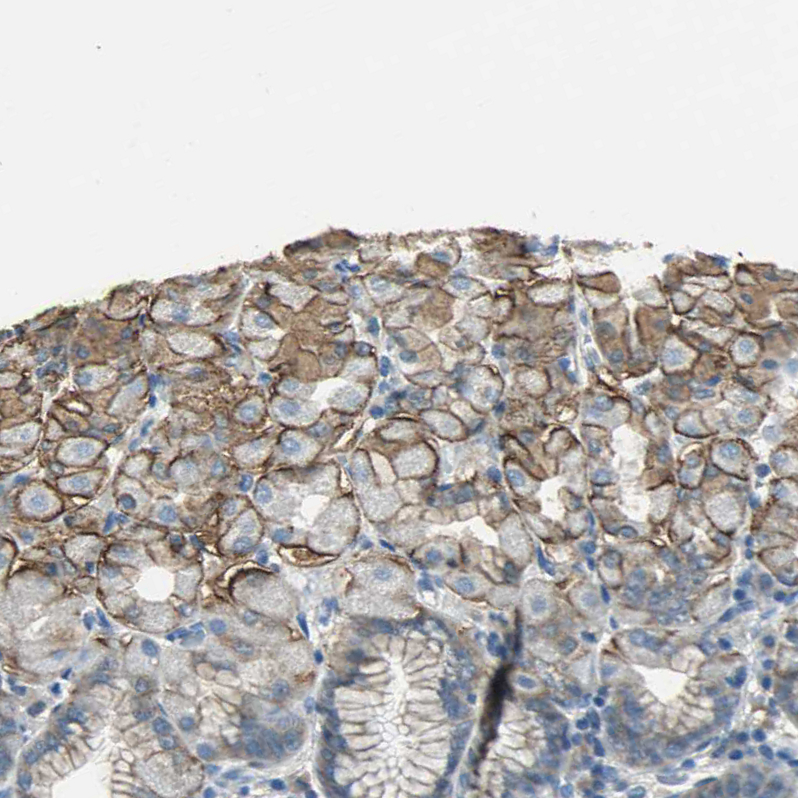

Immunohistochemical staining of human stomach shows strong membranous positivity in glandular cells.